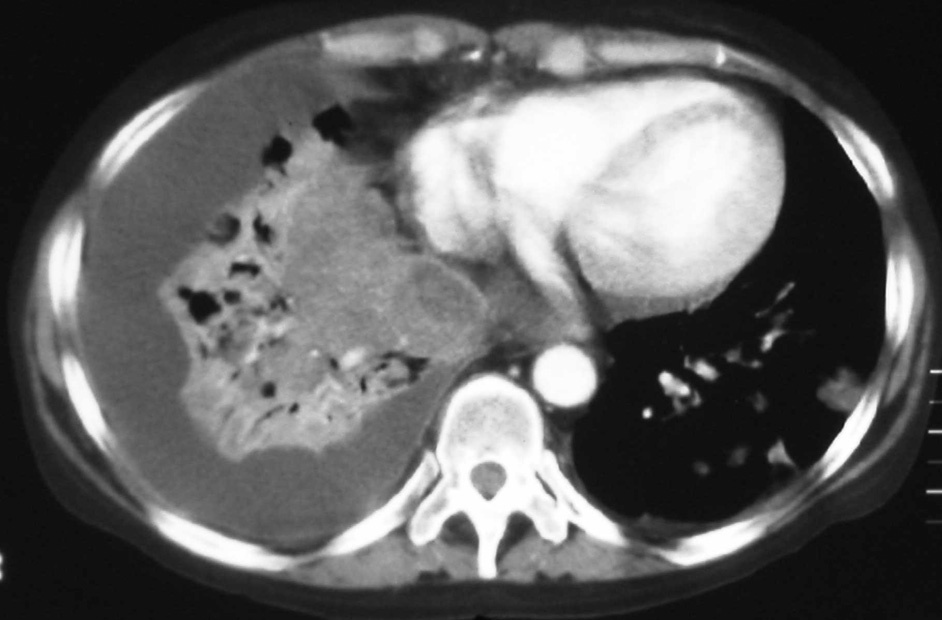

Fig. 4. Tomografía computarizada con contraste intravenoso a la altura de las bases pulmonares.